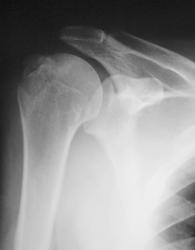

Травма. пациент направлен хирургом в рентгеновский кабинет для рентгенографии плечевого сустава. Были произведены рентгенограммы в двух проекциях. Могу представить, увы, только изображение в прямой проекции.

"Перелом-отрыв бугорка плечевой кости", так любят его наши травматологи, так и называют.

Соглашусь с коллегой Ореховым! Оторвался бугорок!

Ну, и по всей видимости, перелом, без смещения костных отломков.